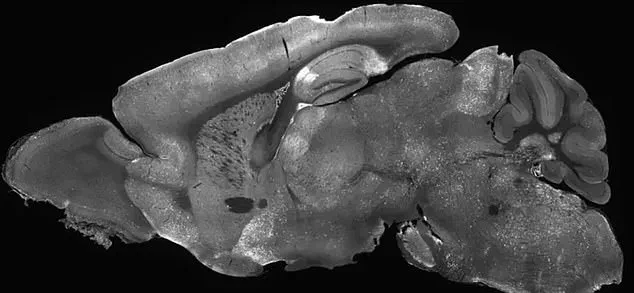

The study on gene therapy for SRDs involved injecting modified adenoviruses into the cerebral ventricles of mice—the fluid-filled cavities in the brain.

This was achieved by inserting a needle through the eye and into the brain, a method that allowed precise delivery of the therapeutic virus.